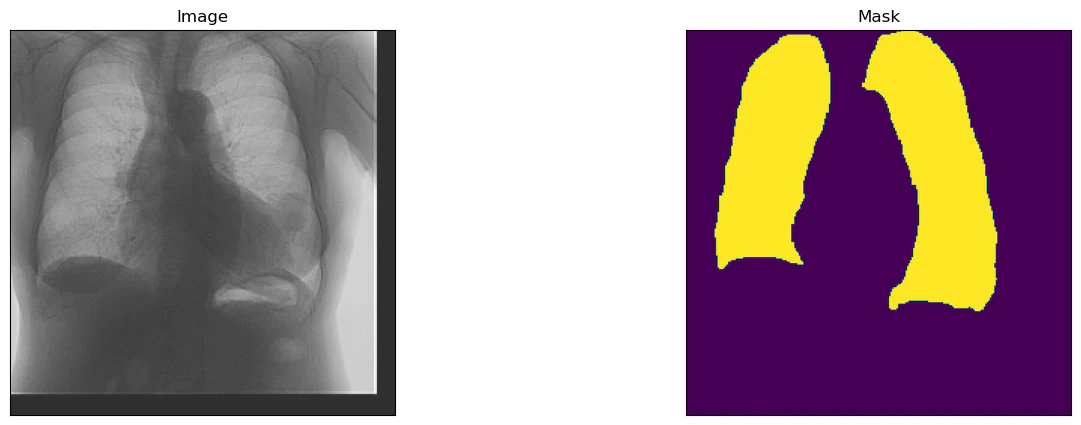

epoch数を40として学習させてみます.20回ほどでIoU値がだいたい0.9あたりに収束していく感じになりました.

ベストモデルを評価用データに適用すると,IoUが0.915程度となり,よく予測できている結果となっています.下記,得られた画像ですが,多少の違いはありますが,おおよその形や場所はとらえられていると思います.